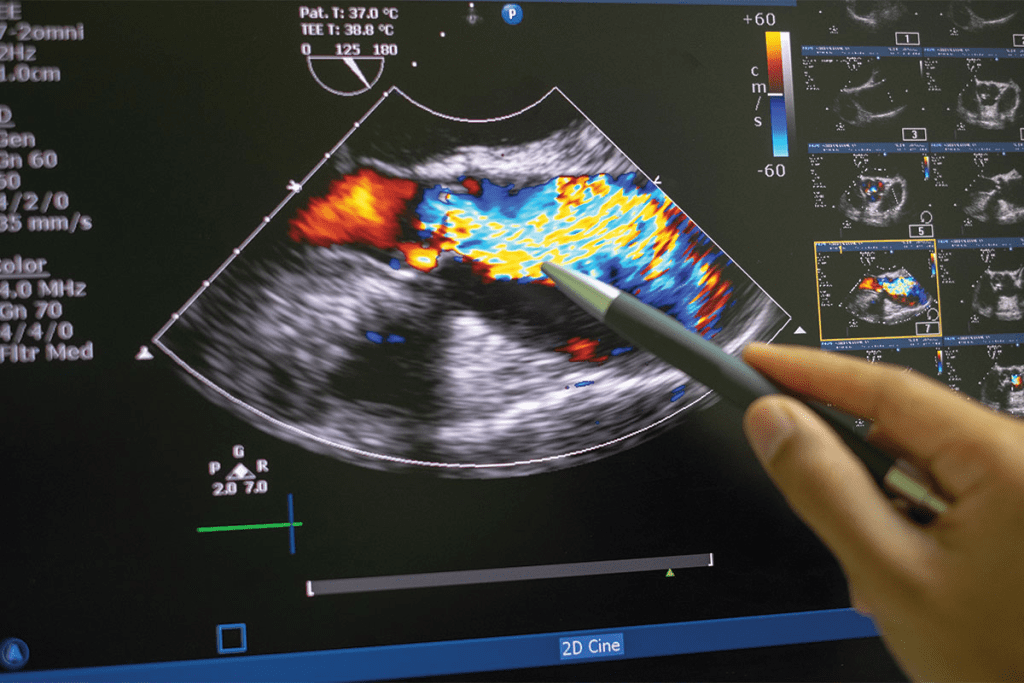

Color Doppler: What Red and Blue Actually Represent

Color Doppler adds blood flow info to the grayscale image. Red means blood is moving towards the transducer, and blue means it’s moving away. This helps doctors check blood vessel health and tumor blood supply.

The color’s brightness shows how fast the blood is moving. Brighter colors mean faster blood flow. This is useful for spotting problems like stenosis or vascular malformations.

Blood flow patterns seen with Color Doppler ultrasound are vital in cancer diagnosis. Malignant tumors show increased vascularity and abnormal blood flow patterns. This shows their aggressive nature.

Using advanced ultrasound like Power Doppler helps see blood flow better. This helps tell if a tumor is benign or malignant.

Doppler ultrasound technology uses Doppler shift to check blood flow. Sound waves change frequency when they hit moving blood cells. This change is shown as colors on the ultrasound: red for flow towards the transducer, and blue for flow away.

Doppler flow signals help check vascular conditions. Doctors use these signals to find blood flow problems. This can help spot issues like cancer.

Tumor Vascularity and Blood Flow Patterns

Tumors grow and spread by getting a blood supply. Tumor vascularity is when new blood vessels form in a tumor. Doppler ultrasound can spot these vessels and check their blood flow.

Malignant tumors have special blood flow patterns. They have more blood vessels and irregular shapes. Doctors can learn about the tumor by looking at these patterns.

When Red and Blue Patterns May Indicate Malignancy

Red and blue on an ultrasound don’t always mean cancer. But, some Doppler flow signal traits can hint at cancer. For example, fast or chaotic blood flow in a tumor might suggest cancer.